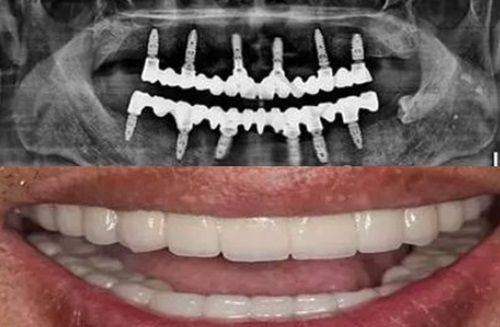

程勇医生擅长的项目十分广泛。在种植技术方面,他精通普通种植、即刻种植、微创种植、微创即刻种植、全口半口牙颌种植等。同时,他还掌握穿颧穿翼种植技术、all - on - 4即刻负重种植技术等多种精良种植技术。在疑难种植治疗方面,他能够处理全口种植义齿、前牙美学种植、骨量不足的种植治疗等各类疑难种植病例。此外,他还擅长侧壁开窗上颌窦底提升手术、自体骨移植手术等其他手术以及种植义齿修复、吸附性全口活动义齿修复等。

程勇医生的特色技术优势明显。他所掌握的各类种植技术,能够根据患者的不同情况,提供个性化的治疗方案。比如在面对骨量不足的患者时,他的复杂骨量不足种植治疗技术以及上颌窦提升等高难度种植手术能力,能有效解决患者的难题。他的数字化3D导板种植技术,能够更加精细地进行种植操作,提高种植的成功几率和精细度。而前牙美学即刻种植技术,则能在解决患者牙齿缺失问题的同时,兼顾美观成效。

程勇医生在患者中口碑出色。有患者称他为“口腔神刀”。曾有患者带年纪大、骨量不足且之前种牙失败过的父亲找程院长做全口种植,程院长凭借专精背景和专精能力,给出明确方案并成功完成种植,让患者全家放心。还有网友表示父亲经程勇院长全口种植牙治疗后,吃饭不再是问题,笑容也变得自然,程院长和他的团队技术好且服务贴心,让全家满意。